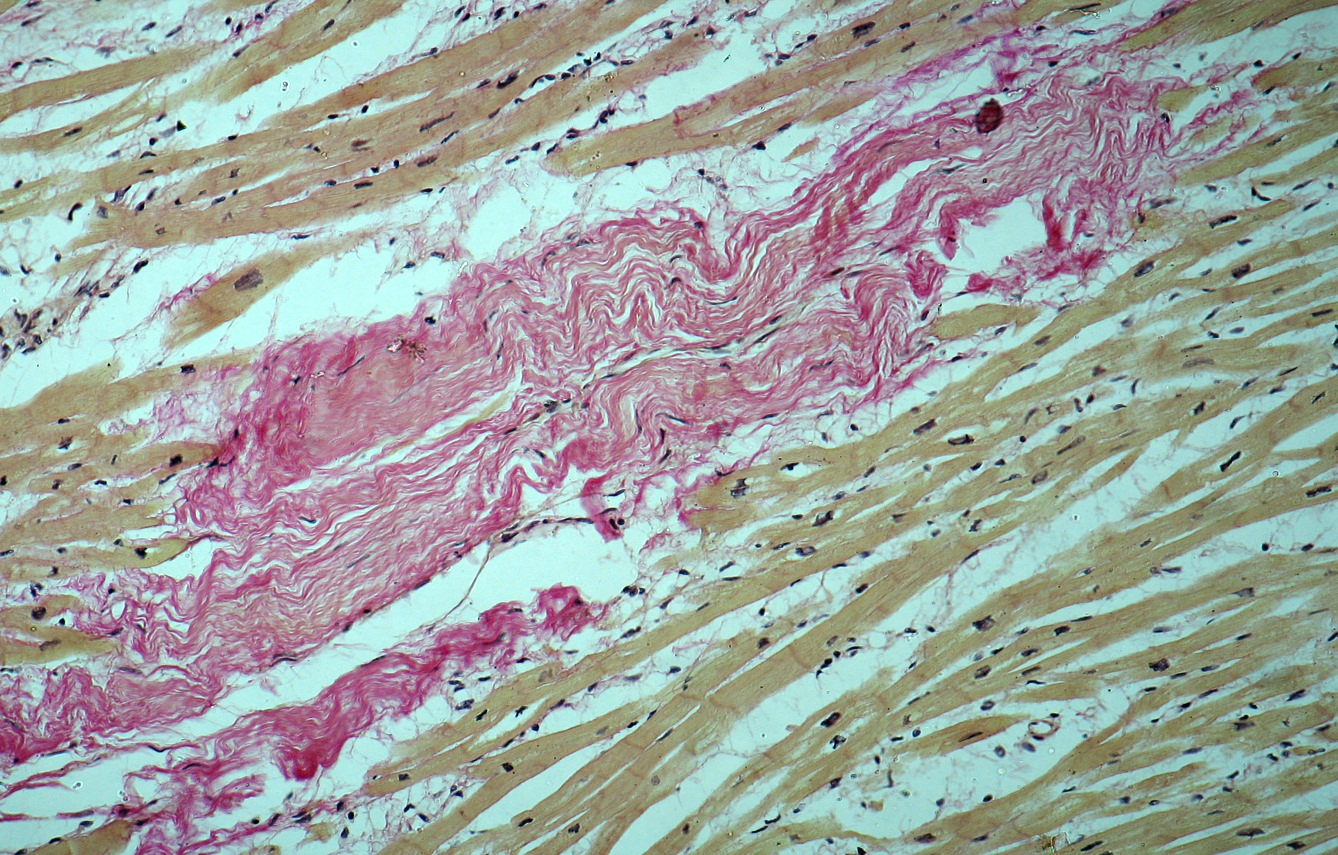

Карнификация Легкого: Микропрепараты и Диагностика

Раздел: Калейдоскоп образов